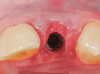

Fig 7. A case (Fig 7 through Fig 16) is presented demonstrating construction of a fixed provisional temporary crown at site No. 10, beginning with an implant placed at the site.

Figure 7